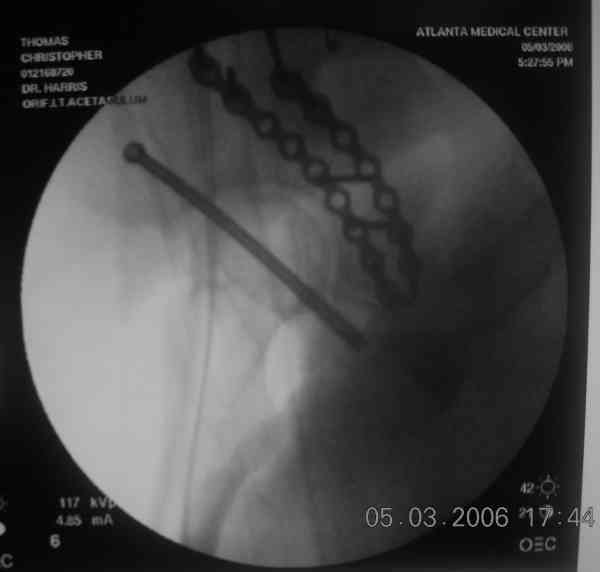

the case that I found is a 20yo male, MCC. his AP pelvis shows an interesting position of his bladder. it is pushed aside by a hematoma from SGA injury. we did a limited lateral window approach for the anterior column first, pt bumped up/supine. then closed and repositioned for KL. I could not find intra-op photos of cases when we did only a small incision for the AC screw (but they do exist!!). the lateral window is available for reduction assessment if a KL approach is being used. in the lateral position this window is available. the prone position definitely takes pressure off of the post column and facilitates reduction. in the lateral position a schantz pin in the ischial tub +/- bone hook in sciatic notch helps with PC reduction. the lateral position also gives better airway access for anesthesia. airway problems are rare, but prone position seems to be a bit more of a challenge to exchange the tube, or reintubate altogether. just something further to debate!

Your lateral intraop image actually made me nauseated... truly a visceral response when I saw it... it's an image which brings back the horrid memories of my past... struggling to achieve my daily malreduction... flipping and flopping the poor patient... reprepping... wasting time... praying... trying to get a C-arm in place... gag... until some kind soul taught me a prone KL.... ahhh, what a great day that was.